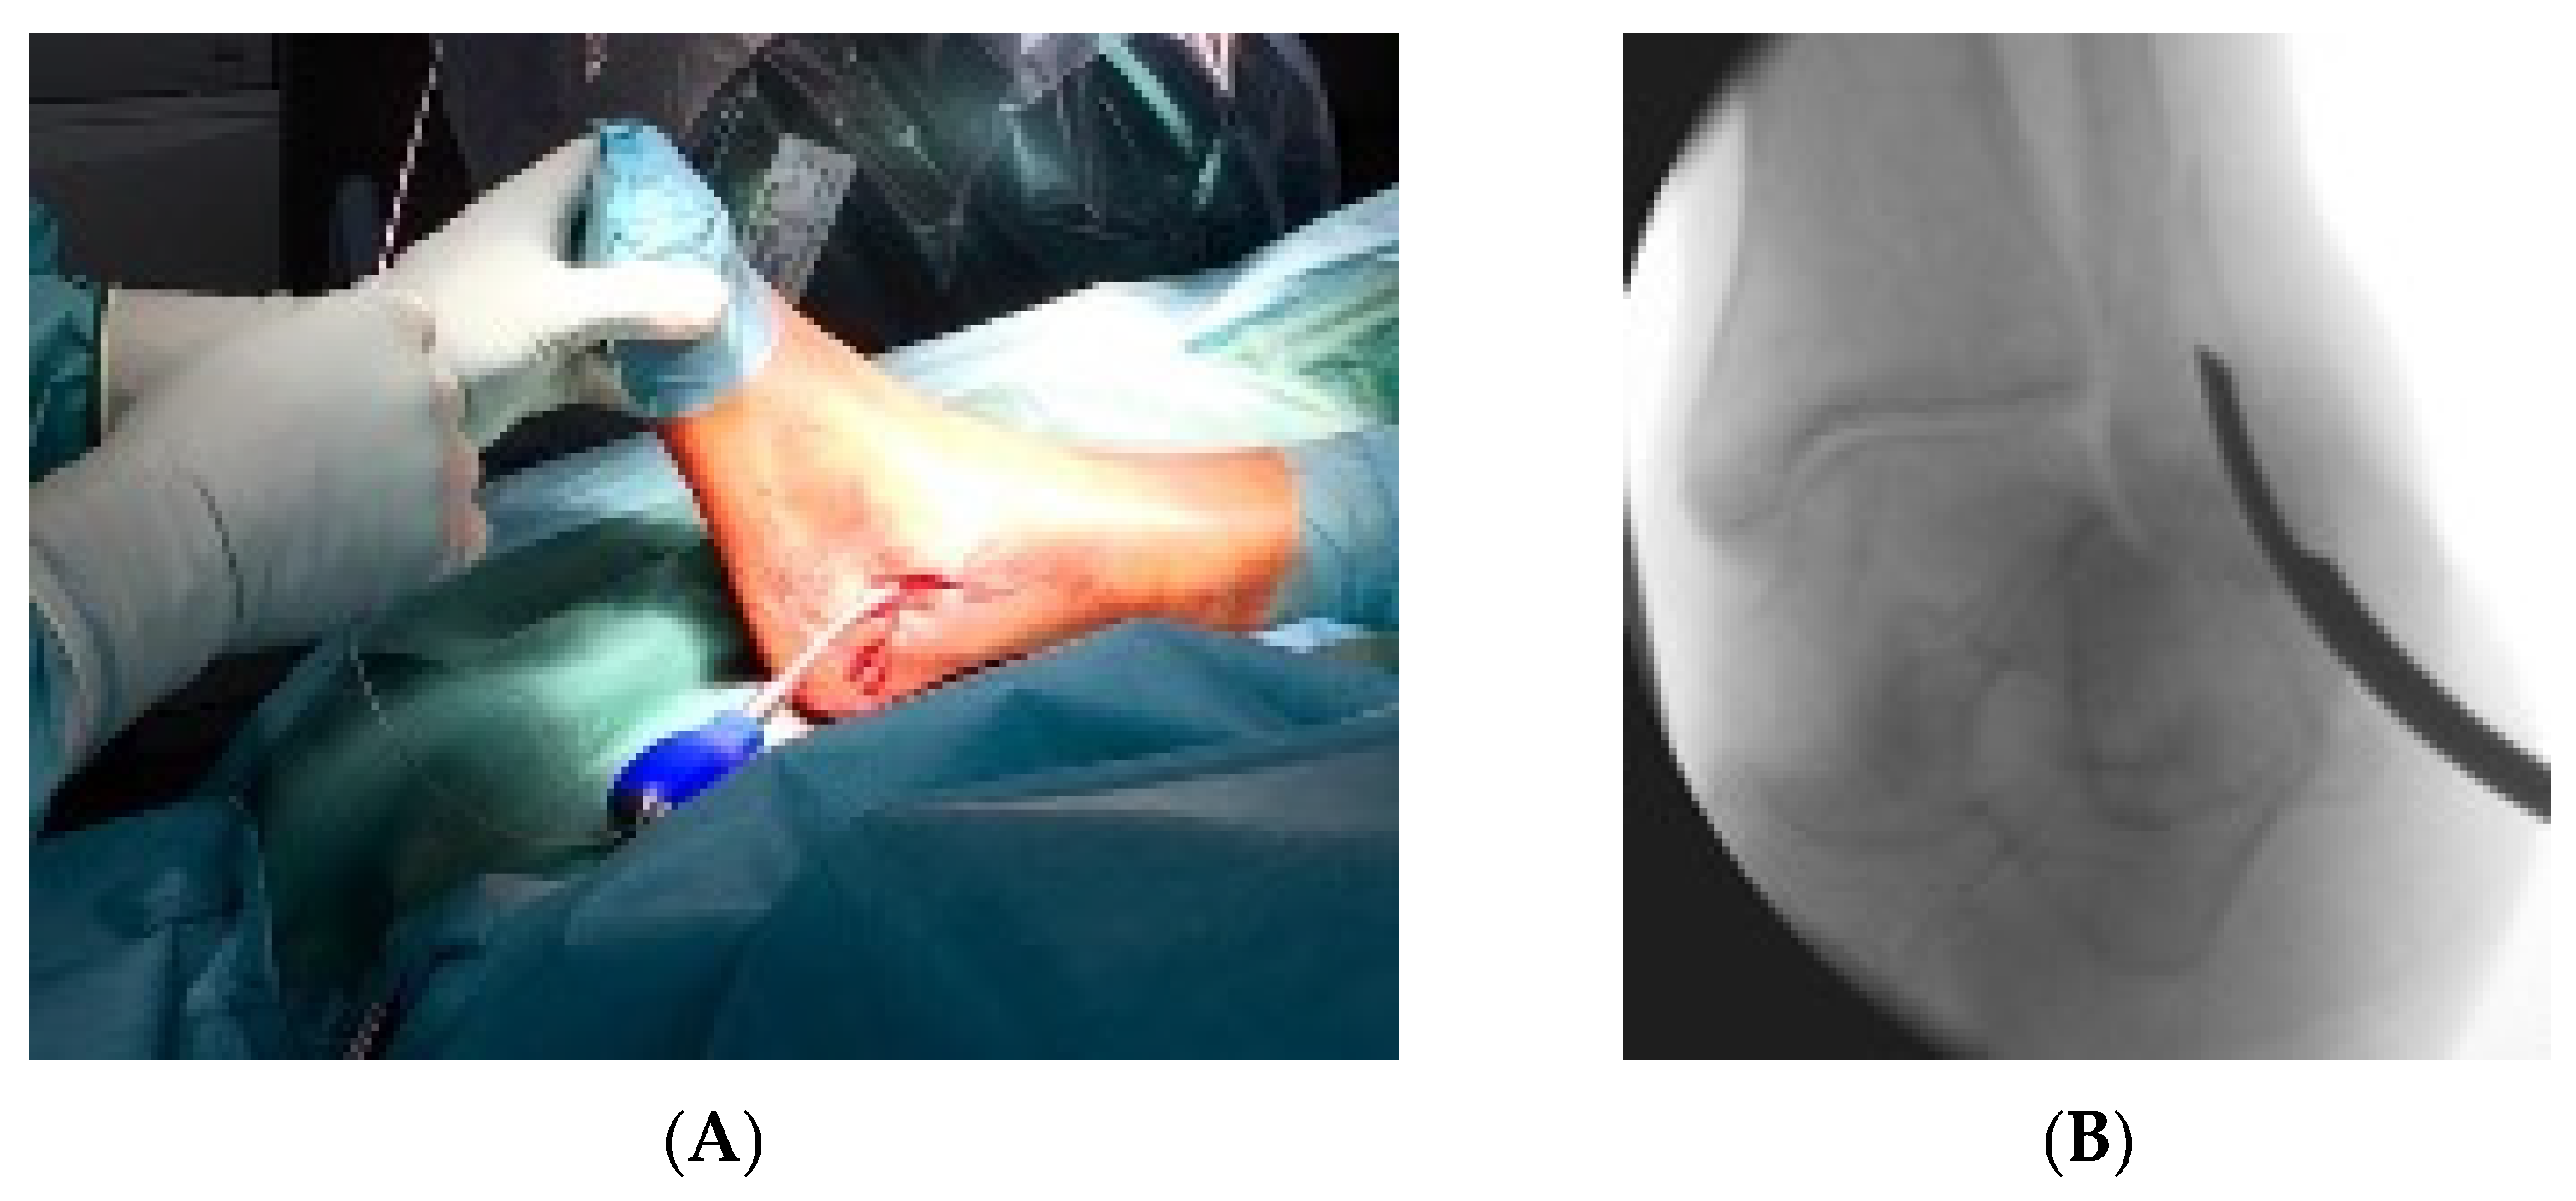

2.2. Surgical Technique and Postoperative Therapy

- Zyskowski, M.; Crönlein, M.; Heidt, E.; Biberthaler, P.; Kirchhoff, C. Osteosynthesis of distal fibular fractures with IlluminOss: Video article. Unfallchirurg 2017, 120, 6–11. [Google Scholar] [CrossRef][Green Version]